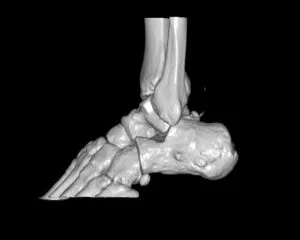

CT

GE社製Revolution ACT(16列)を導入しています。X線を利用して体の断面(輪切り)を撮像する検査です。この輪切りの画像をコンピューターで処理することにより、様々な方向からの断面像や3D画像を得ることができます。

CTで検査した画像